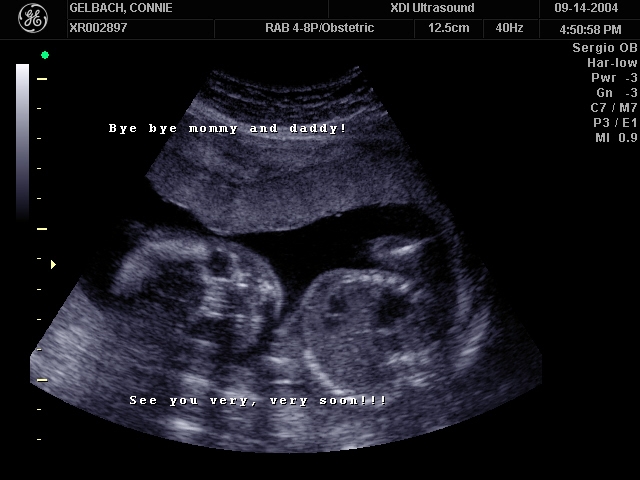

Sonograms